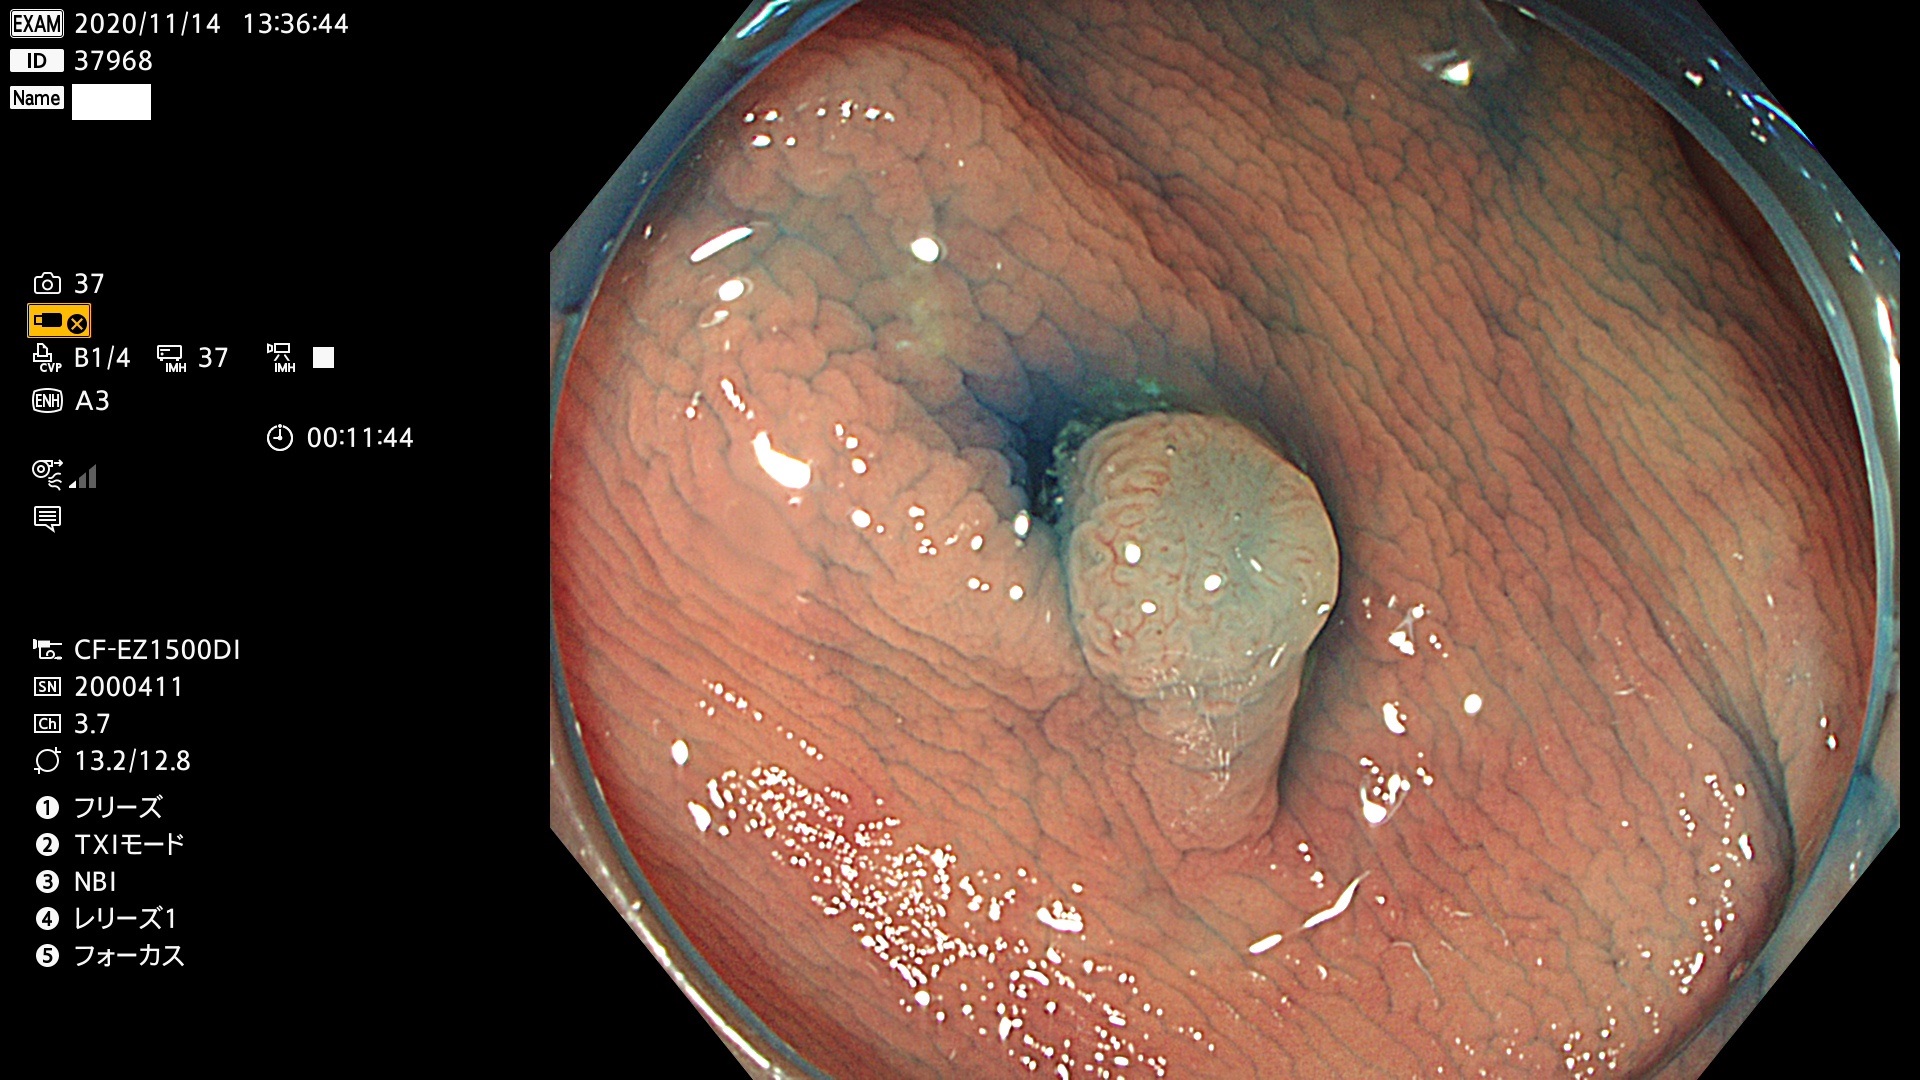

腺腫発見率 78  % (カルテ番号 37900〜37999の100名の方の検査結果で集計)

37900 37902 37903 37904 37905 37906 37907 37909 37910 37911 37912 37913 37914 37915 37916 37917 37919 37921 37922 37923 37926 37928 37929 37930 37931 37933 37934 37935 37936 37937 37938(SSAPのみ) 37939 37940 37941 37942 37943 37946 37947 37948 37949 37951 37952 37953(SSAPのみ) 37955 37956 37957(SSAPのみ) 37958(SSAPのみ) 37960 37962 37963 37964 37966 37967 37968 37971 37972 37973 37975 37976 37977 37979 37982 37983 37984 37985 37986 37987 37988 37989 37990 37991 37992 37993 37994 37995 37996 37998 37999

発見困難で危険性の高い平坦型病変(上記100名より抽出)